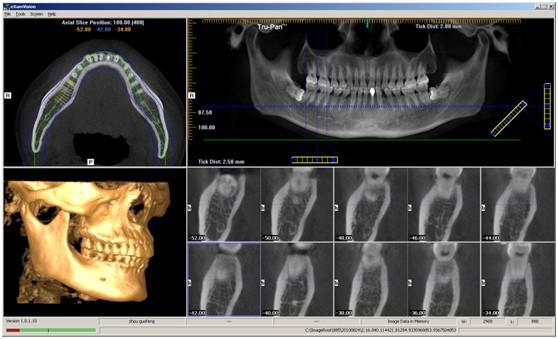

杭州牙科医院新引进的即刻种植技术,利用3~4毫米的小切口,将人工牙根“种”入口腔内,摆脱了传统种植牙切开翻起牙肉、缝合、拆线等步骤,将创伤降低到最小程度,大大减少了肿痛和出血量。具有数字化精准预测定位、10分钟种植、堪比真牙、使用寿命长等特点,势必成为种植牙技术的新风向标。